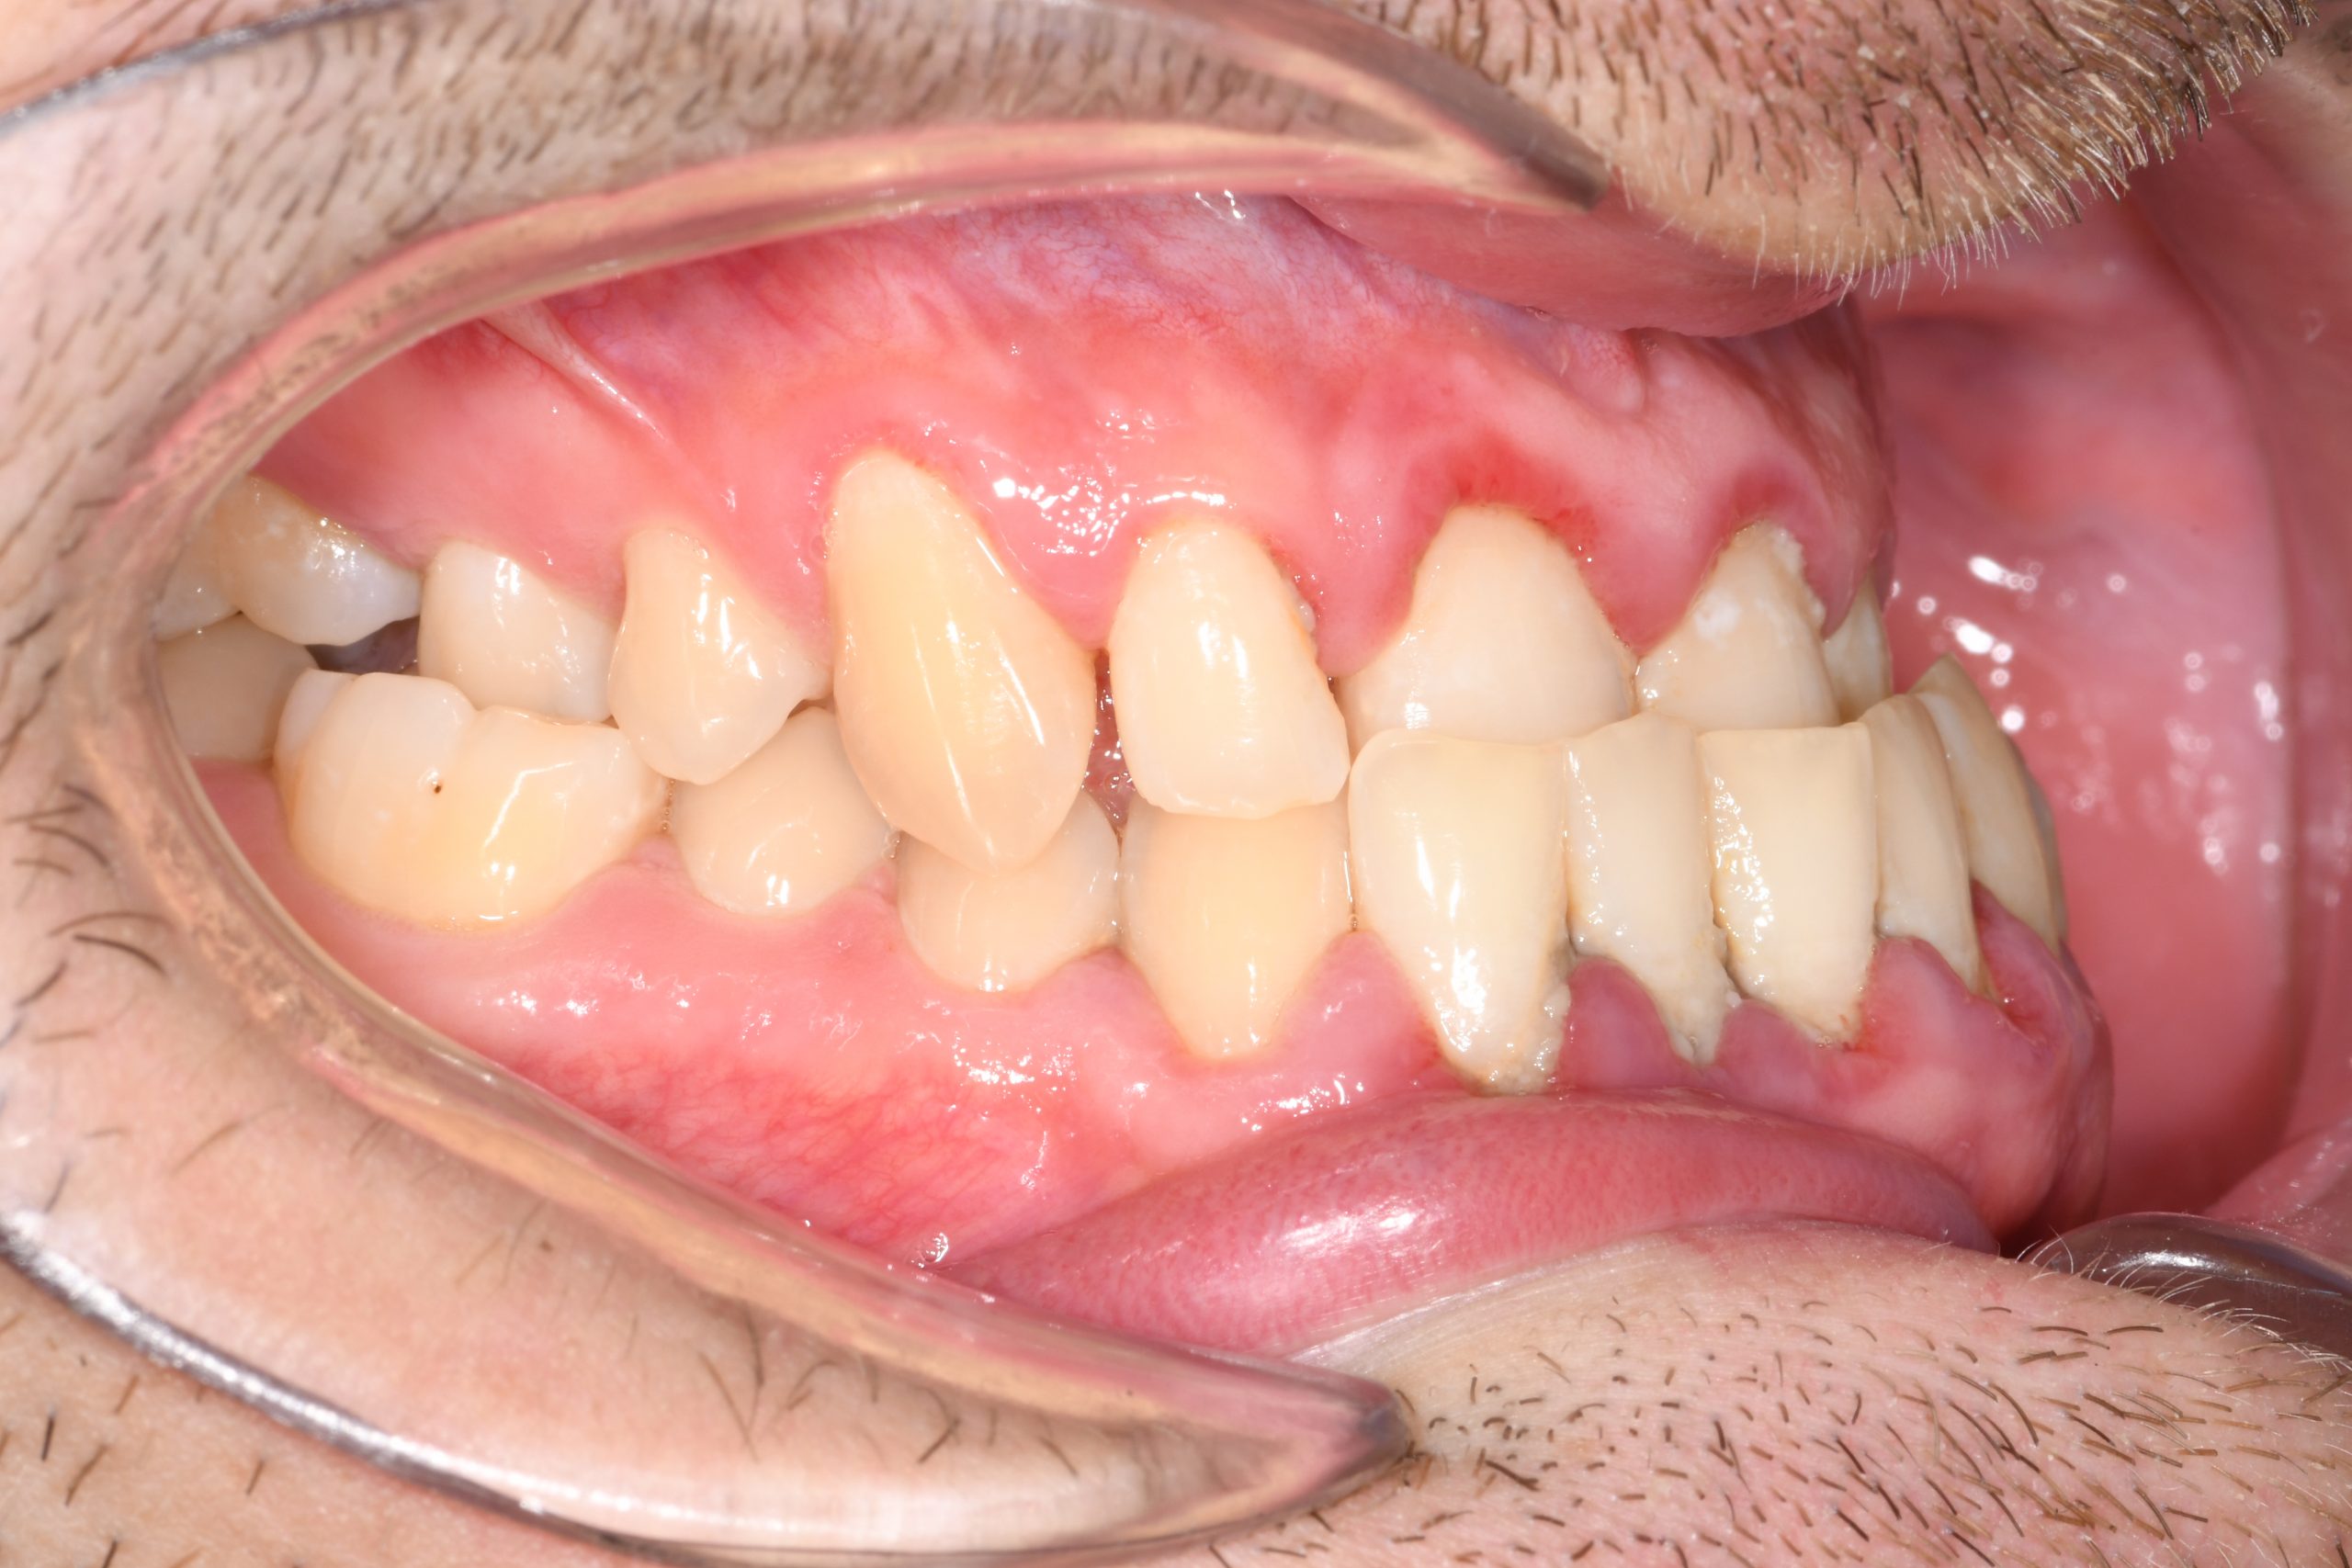

Az elmúlt évekből rengeteg szakmai referenciát tudnánk bemutatni, amelyek különböző fogszabályozási problémákat oldottak meg. Válogatva a több száz esetből, ezen az oldalon olyan képeket, információkat igyekeztünk bemutatni, amelyeknek a segítségével a jövőbeni pácienseinknek azt tudjuk üzenni: A Te fogsorod is lehet gyönyörű!

(Képeket a Pácienseink külön írásos beleegyezésével mutatjuk be!)